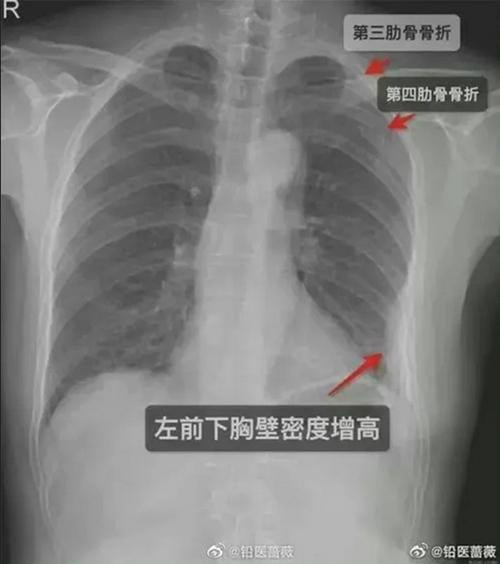

Nào ngờ, cô gái thấy ngày càng đau hơn, nên 5 ngày sau, cô đành tới bệnh viện kiểm tra. Các bác sĩ chụp X-quang và phát hiện ra rằng cô bị gãy xương: Không phải một, mà là 3 xương sườn bị gãy - 2 xương bên phải và một bên trái. Cô gái buộc phải nghỉ làm một thời gian để điều trị, thế là thu nhập thì không có trong khi tiền viện phí, thuốc men và thuê người chăm sóc thì tốn kém.

![]() |

| Hậu quả của cái ôm chào hỏi là 3 xương sườn bị gãy. Ảnh: Sina. |